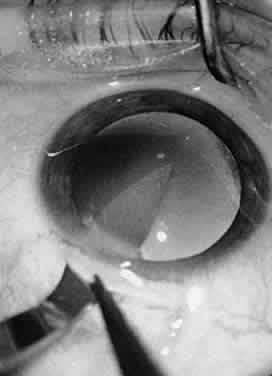

Fig. 31. A viscoelastic material may be used to reform the capsular bag after cataract extraction. The viscoelastic material is used to stabilize a space within the eye or to occupy a potential space.

In ophthalmic surgery, viscoelastic materials may be used for many different purposes. Viscoelastic materials are used to protect tissues by providing a protective coating. For example, in the anterior chamber, viscoelastic materials may be used to protect the endothelium during phacoemulsification. Viscoelastic materials also may be used to stabilize a space within the eye or to occupy a virtual space within the eye. Viscoelastic materials may be used to reform the capsular bag after cataract extraction, aiding in the insertion of IOLs (Fig. 31). Additionally, these materials may be used to separate adherent tissue layers when they are introduced through a cannula to lyse synechiae. In some instances, the viscoelastic material may be used to reappose tissues, for example, to replace a detached Descemet's membrane. Finally, a viscoelastic material may be used to occlude or seal the anterior chamber. This technique can be useful during repair of corneal lacerations or when applying tissue adhesive for small corneal perforations.10